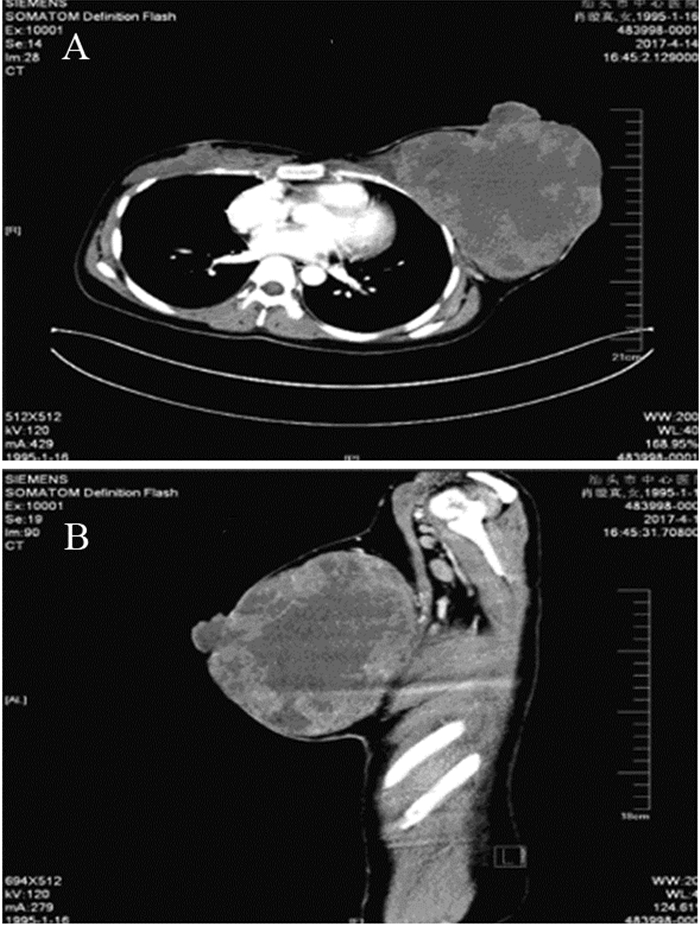

生长迅速的年轻女性乳腺恶性叶状肿瘤1例报道

图片尺寸700x926